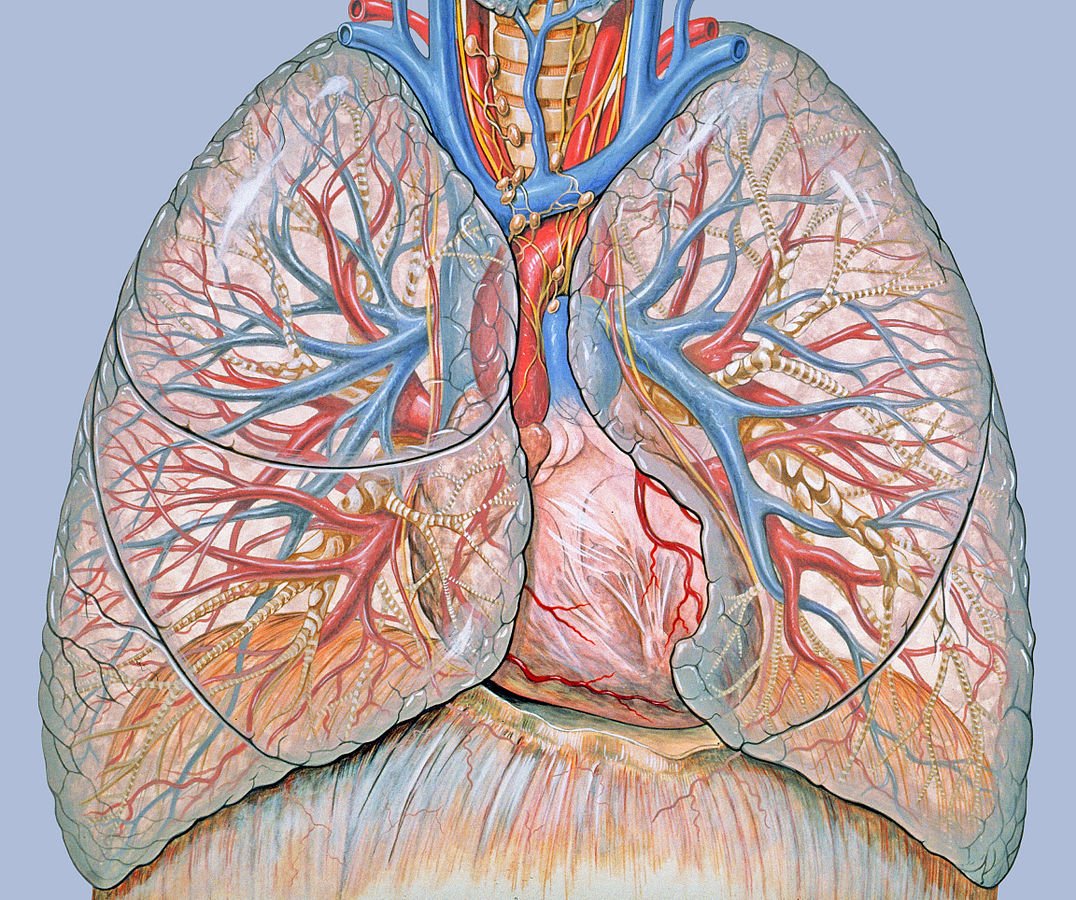

What is the effect of body mass index on pulmonary function in kids? http://bit.ly/2hyuqpR